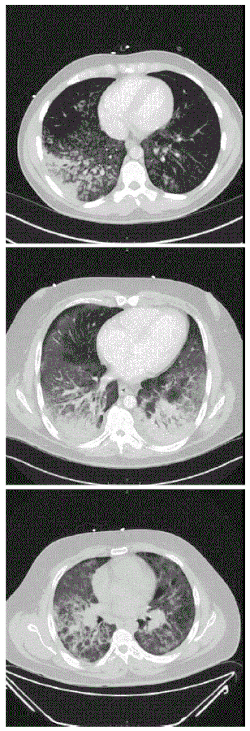

| CT scan of the chest showing diffuse lung infiltrates found in three cases of vaping-associated pulmonary injury | |